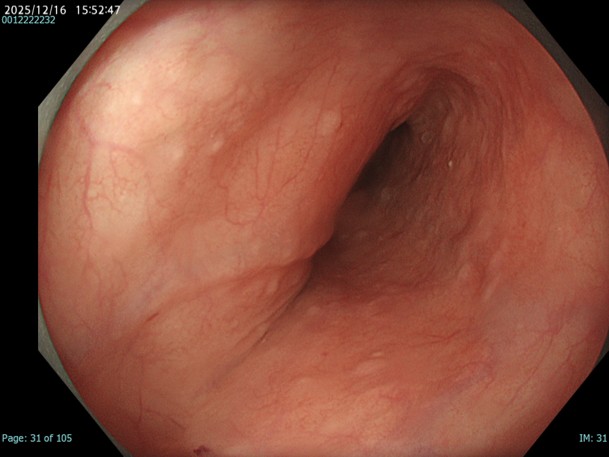

• 白色光観察(中遠景)

強調設定:A3

図1

胸部中部食道でやや粗造で血管透見が落ちているが、明かなDLは指摘が困難であり、色調も周囲粘膜とほぼ同等の為、この画像のみで腫瘍性変化を診断することは困難である。